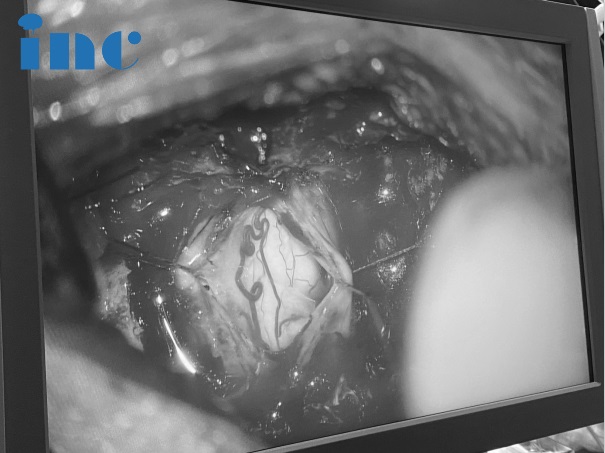

脊髓手术技术难度之大,决定了其对于术者的操作要求高。治愈或致残,往往就在手术刀所到之处的毫厘之间即见分晓。而INC德国巴特朗菲教授在国内医生的配合以及相关术中神经电生理监测等高科技设备的辅助下,于狭窄的方寸之内一层层剥离肿瘤,手术手法细致温柔,脊髓肿瘤被完整切除了下来。

手术主要的目的是脊髓功能保护与恢复,在保护脊髓功能的前提下,顺利分离肿瘤-脊髓界面尽量全切肿瘤。术中操作轻柔,力求最小程度牵拉脊髓,始终注意保护正常的脊髓。严格沿后正中沟切开脊髓,避免损伤脊髓。结合术中电生理监测,避免损伤重要神经;术后激素冲击治疗,减轻脊髓的继发性损伤。

术中显微镜仔细观察肿瘤形态

术中全神贯注剥离肿瘤

术中测量肿瘤大小与影像图片中的大小进行对比,确保切除干净

全切肿瘤后的颈髓